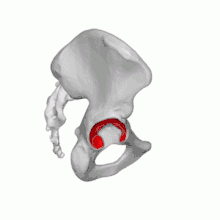

Fractures du cotyle

Les fractures du cotyle peuvent résulter d’un choc sur la région trochantérienne (bord externe de la hanche), la tête fémorale est alors poussée dans le bassin (chute sur le trochanter, de sa hauteur pour la personne âgée, chute de plus grande hauteur pour le sujet jeune)[8],[12].

Elles peuvent aussi résulter d’un choc dans l’axe du fémur : typiquement lors d'un accident de voiture où le genou du conducteur vient heurter le tableau de bord, provoquant une luxation postérieure de hanche avec fracture du rebord postérieur du cotyle. Ce type de lésion, survenant sur le sujet jeune par accident à haute énergie cinétique, a été réduit de façon significative par l'obligation de porter la ceinture de sécurité[12].

Les fractures du cotyle dépendent de la classification de Judet-Letournel, établie en 1964, et qui reste le gold standard au XXIe siècle[12].

Dans cette classification, l'os iliaque est considéré comme formé de deux colonnes : l'une antérieure ou ilio-pubienne, l'autre postérieure ou ilio-ischiatique, réunies par une clé de voûte : le toit du cotyle.

Les fractures du cotyle sont alors classées en dix catégories réparties en deux groupes (fractures élémentaires et fractures complexes) :

- Les fractures élémentaires concernent une seule colonne, antérieure ou postérieure, elles sont souvent associées à une luxation de hanche. Les auteurs en distinguent cinq : fracture du rebord postérieur, de la colonne postérieure, de la paroi antérieure, de la colonne antérieure, et la fracture transversale.

- Les fractures mixtes ou complexes, associant deux ou plusieurs fractures élémentaires, avec fracture des deux colonnes, décrites aussi en cinq variétés[12].